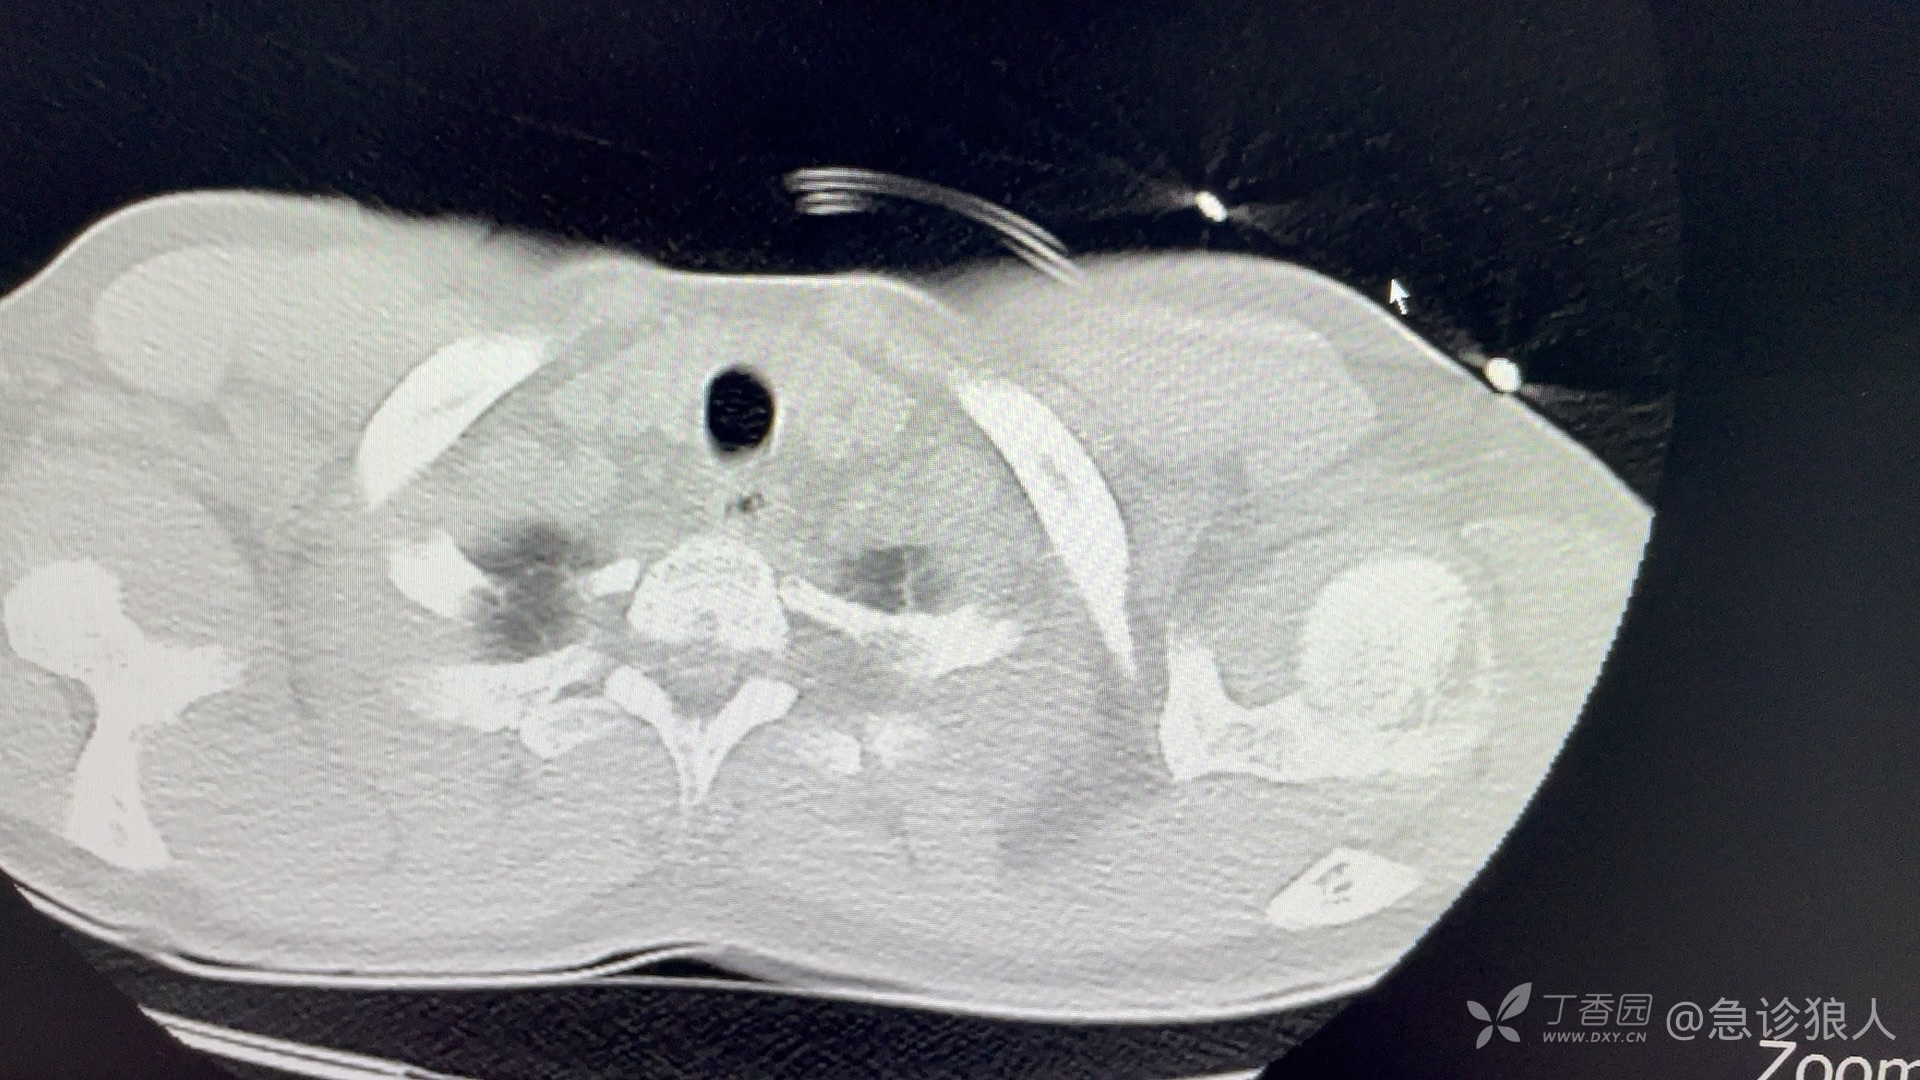

患者、男、23岁!

最后的微信是,“姐,我爱你,来世再见!”

这个肺,应该是不能来世再见了!